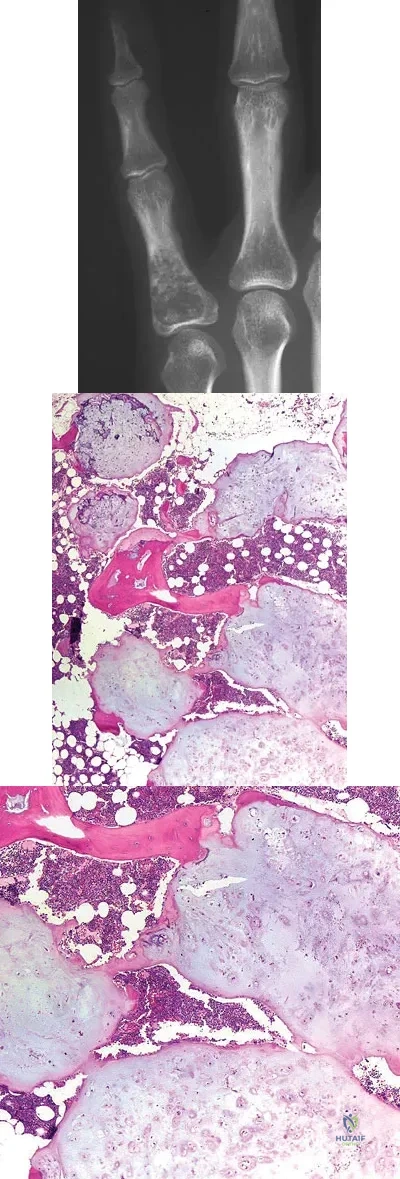

A 28-year-old woman has had pain in her hand and mild swelling of the little finger for the past 2 months. A radiograph is shown in Figure 41a, and the biopsy specimen is shown in Figures 41b and 41c. What is the most likely diagnosis?